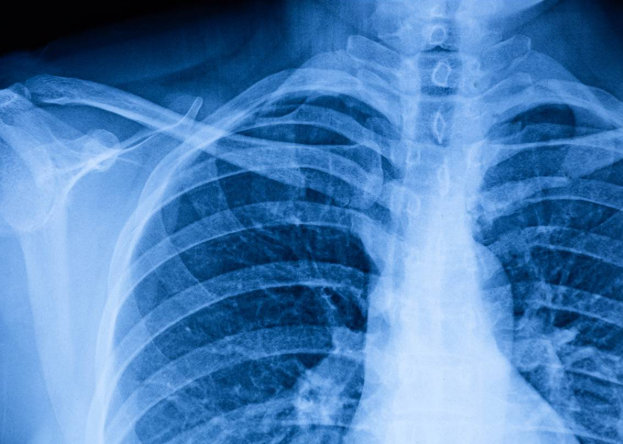

폐결절은 폐 안에 생긴 3cm 이하의 고형성 음영 또는 병변을 말합니다. 일반적으로 건강검진에서 시행하는 흉부 X-ray에서는 발견되지 않는 경우가 많으며, CT 검사에서 우연히 발견되는 경우가 많습니다.

폐결절 CT 검사: 왜 반복해야 할까?

폐결절을 발견하고 나면 병원에서는 일정 주기의 폐결절 CT 추적검사를 권장합니다. 그 이유는 결절의 크기 변화, 모양의 변형, 새로운 결절의 발생 여부 등을 관찰하기 위함입니다.

CT 촬영 시 사용하는 방사선 양이 걱정될 수 있지만, 최근에는 저선량 CT가 활용되어 그 부담이 많이 줄어든 상태입니다. 방사선 노출보다 중요한 것은 결절의 진행 여부를 놓치지 않는 것이기에, 권고 일정에 맞춰 촬영을 진행하는 것이 좋습니다.